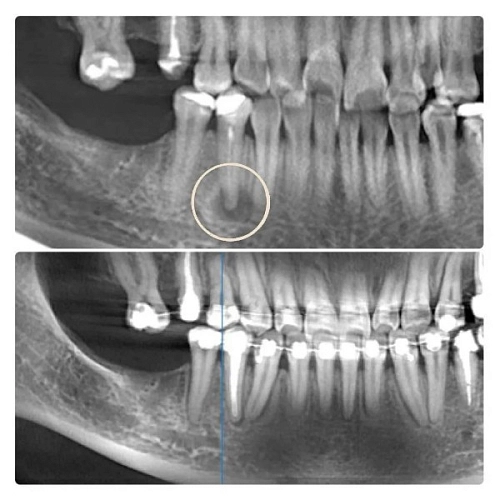

В данном клиническом случае пациент жаловался на боль в зубе.

Компьютерная томография показала воспаление у корня зуба на верхней челюсти слева. Причиной воспаления стал пропущенный канал в зубе.

На снимке положительная динамика через 1 год